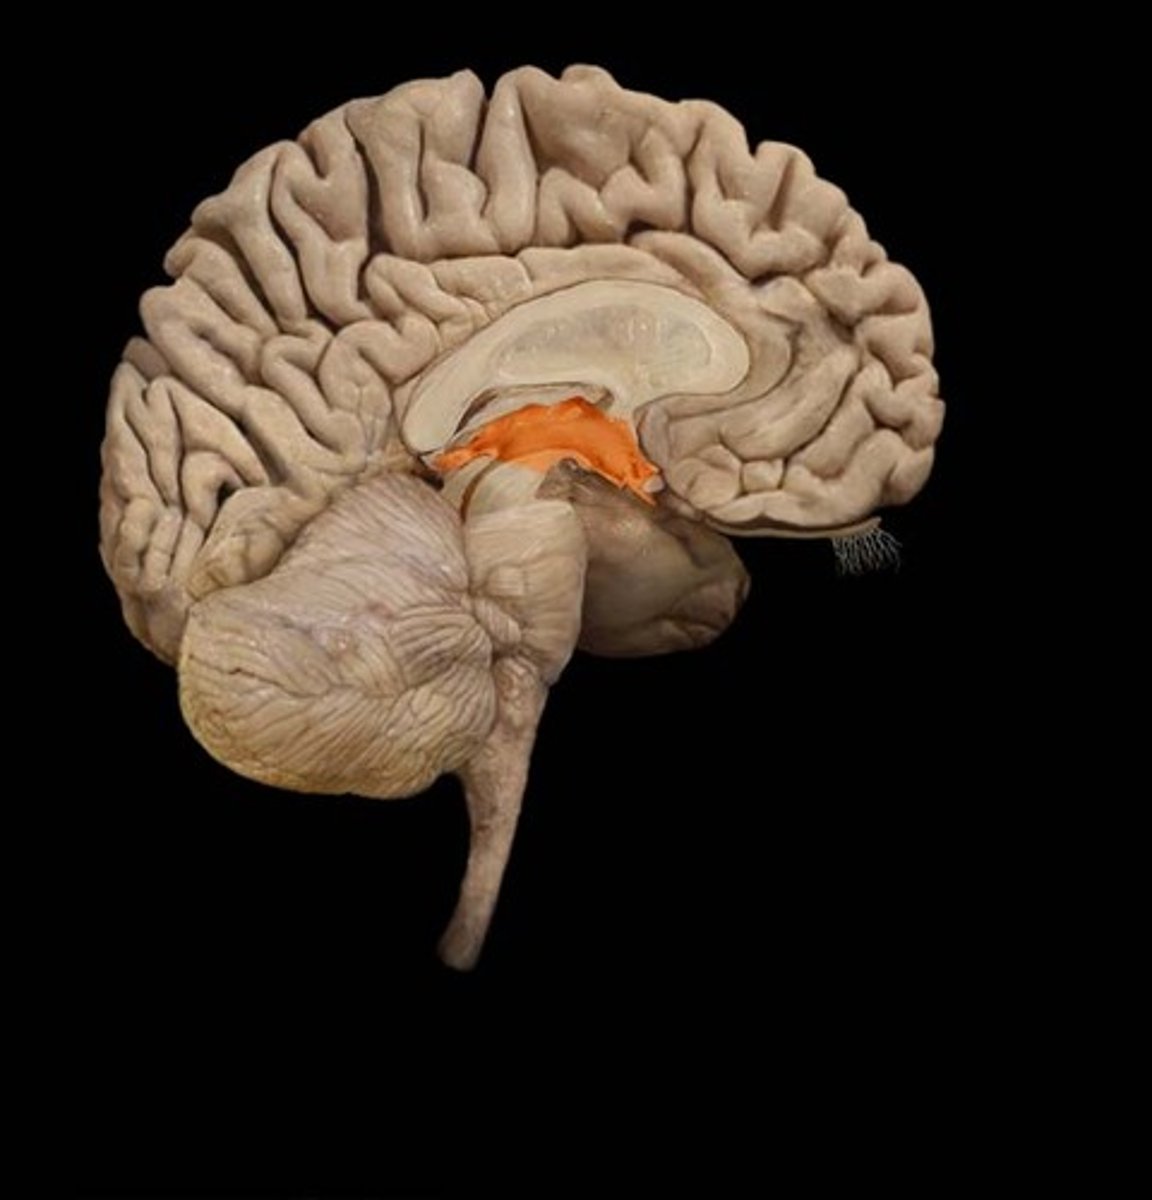

Flocculonodular Lobe

A region of the cerebellum; involved in control of postural reflexes

Associated with the thalamus

Flocculus

Small but dense lobe involved in eye movements and balance

Nodule

Medial protrusion seen on the midsagittal view of the cerebellum; part of the vermis

Cerebrocerebellum

Vestibulocerebellum

Vermal Zone

Composed of flocculonodular lobe

Controls eye movement and axial musculature related to balance and posture

Connects two hemispheres of cerebellum

Spinocerebellum

Enhances muscle tone and coordinates skilled, voluntary movements